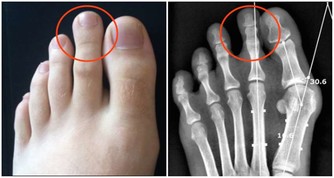

1. 你的肌肉感覺無力

鉀對於血糖轉化為糖原(一種儲存在肌肉和肝臟中的燃料)是必不可少的,因此當血糖水平低時,你可能會一整天在學習或工作時感受肌肉無力。另外,鉀水平較低也可能導致尿液中排泄過多的鈣,這也會影響你的骨骼健康。